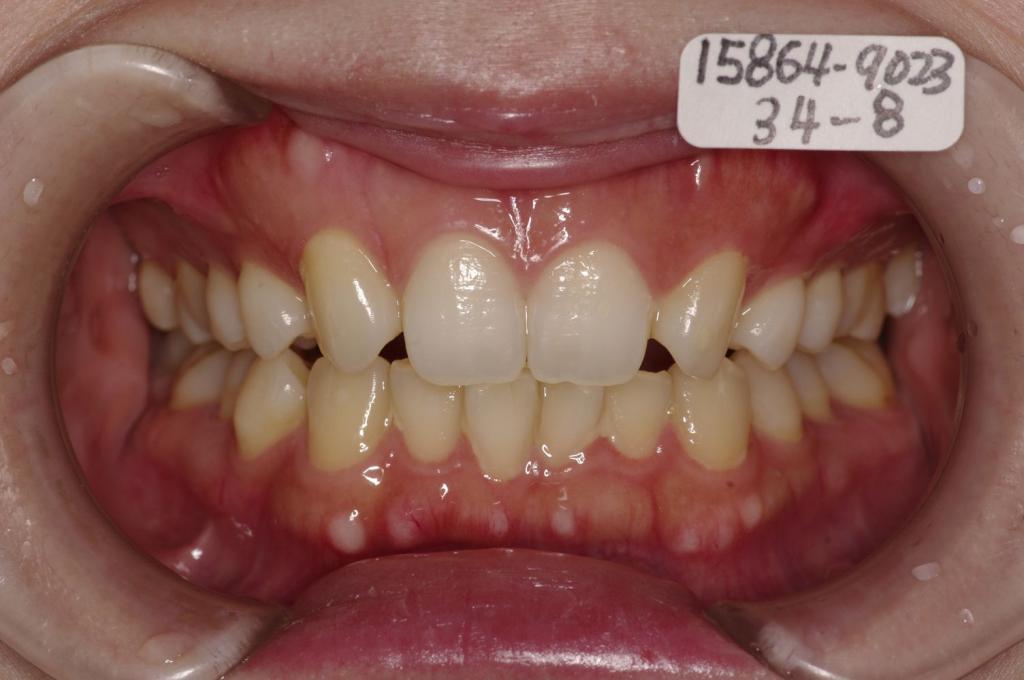

歯欠損の矯正治療

(治療期間、治療前後写真、治療方法、費用)WORKS

下記の実績データをクリックして頂くと「性別」、「治療開始年齢」、「治療終了年齢」、「治療方法(矯正治療装置写真含む)」、「治療終了までの費用」など、詳細な矯正治療データをご覧頂けます。